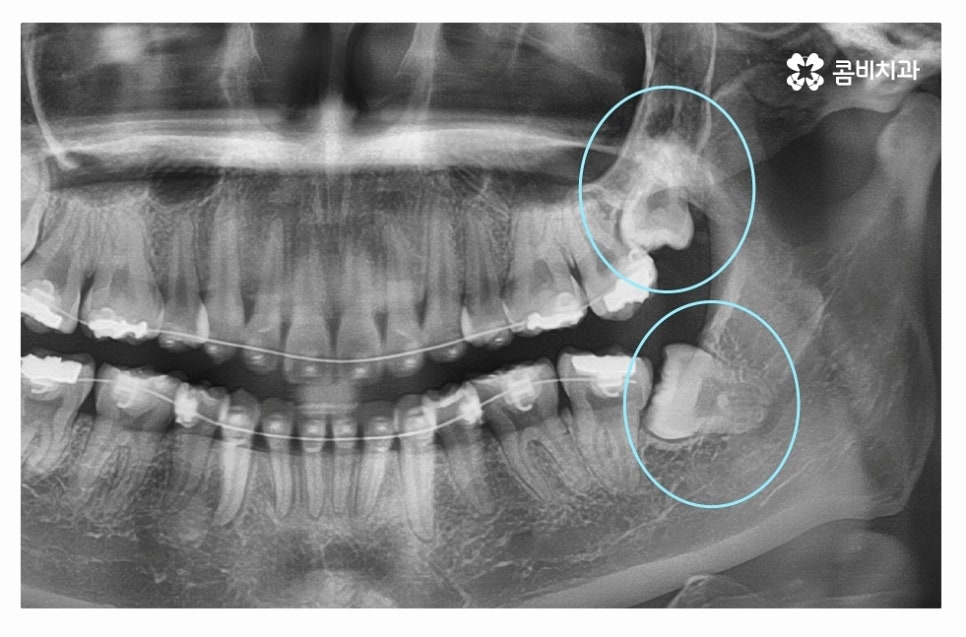

다음 사례를 살펴보면 위 사례와 마찬가지로 사랑니가 정상적으로

맹출 되어 있지 않고 어금니 뿌리 쪽으로 자라고 있는데요

위 환자분의 경우 사랑니와 어금니 사이에 충치가 발생하여

어금니 손상까지 (엑스레이상 좌측 위 사랑니) 유발된 사례라고 할 수 있어요.

사랑니의 경우 발치를 하면 되지만 어금니는 평생 지켜야 한다는 점에서

치아 수명이 줄어들게 되니 안타까운 상황이라고 할 수 있는데요.

사랑니로 인해 충치가 발생한 좌측 위 사랑니도 발치를 진행했지만

우측 사랑니도 위치가 좋지 않아서 누운사랑니발치 진행하였고

사랑니로 인해 충치가 발생된 어금니의 경우 크라운 치료를

해야 했던 만큼 사랑니는 주기적으로 검진이 필수라고 할 수 있어요.